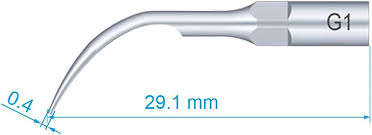

GDC Single End Probes #1 (Pcp11.5b)

The Screening probe has a 0.5 mm ball at the tip and a color-coded area 3.5 to 5.5 mm from the tip. It has markings mm 3.5-5.5-8.5-11.5. The ball at the end of the probe is intended to enhance patient comfort and assist in detecting overhanging margins and subgingival calculus

- Type: Single End Probes

- Category: Periodontics

- Material: Stainless Steel